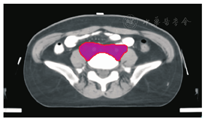

笔者所在科室对于FIGO临床分期为ⅡB期宫颈癌(阴道穹窿受侵、宫旁受侵近盆壁)的调强放疗流程及靶区CTV勾画范围建议如下。对其定位前准备工作包括:患者于定位前30~40 min排空膀胱,再饮水500 mL(含造影剂碘化醇10 mL),显影小肠。对其靶区CTV勾画具体操作步骤为:让患者取仰卧位,身下垫胸、腹平板,双手抱肘并上抬置于额头,热塑体膜固定(上腹至大腿上约1/3处);待热塑体膜冷却成形后,激光灯下于体前正中和两侧分别置铅点(尽可能靠近靶区中心)。此时尽可能行CT增强扫描,以更清楚显示解剖位置;对造影剂过敏、高龄、伴有严重并发症等不适合行CT增强扫描者,仅进行平扫。CT检查的扫描范围为:第一腰椎体上缘至坐骨结节下2 cm,层厚为5 mm,若腹主动脉旁淋巴结转移,则上移至隔顶;若全阴道浸润、腹股沟淋巴结转移,则下移至外阴下4 cm。其中,对靶区CTV勾画:放疗前,应常规实施CT、MRI或PET-CT检查,以明确肿瘤靶区范围及是否存在远处转移(部分远处转移病变,可与原发部位同时进行放疗)。对于其GTV勾画,则包括临床肉眼可见或可触及的,或可通过检查手段证实的肿瘤区域,具体包括宫颈肿瘤、受侵宫旁及阴道组织。MRI检查是确定软组织及宫旁受侵的较理想方法。若腹膜后淋巴结转移,需对淋巴结照射剂量进行加量时,CTV则应单独勾画转移淋巴结靶区。CTV勾画分为局部肿瘤区域和淋巴引流区域。局部肿瘤区域CTV勾画,包括局部肿瘤GTV及显微镜下可见的亚临床肿瘤病变,首先为宫颈、宫体、宫旁和阴道CTV勾画。①宫颈CTV:勾画全部宫颈。②宫体CTV:勾画全部宫体。③宫旁CTV:勾画上界为乙状结肠跨过子宫及输卵管处,下界为泌尿生殖膈,前界为膀胱后壁/髂外血管后缘。若子宫前倾明显,则子宫前界为宫旁前界,后界为宫骶韧带和直肠系膜前缘,内侧界为子宫颈阴道,外测界为骨盆壁,不包括肌肉和骨。值得注意的是:若宫骶韧带受累,CTV勾画则需将整个宫骶韧带全部包括在内,此时直肠系膜淋巴结及直肠周淋巴结均应包括在内。对于FIGO临床分期为ⅢB期及以上者,CTV应将直肠周淋巴结勾画在内,宫旁靶区与髂淋巴结及闭孔淋巴结区重叠。④阴道CTV:若阴道无受侵,则勾画阴道上段1/2,若上段受侵,则勾画阴道上段2/3,若阴道广泛浸润,则勾画全阴道。其次,盆腔淋巴结引流区包括宫颈旁、宫旁、闭孔、髂内、髂外、骶前及髂总淋巴结CTV勾画,依照其血管走行进行勾画。①髂总动脉CTV:上界为腹主动脉分叉下缘,下界为髂总动脉分叉下缘;前界为血管前7 mm,后界为血管后7 mm;内侧界为血管内侧7 mm,外侧界为血管外7 mm,腰大肌内侧缘,包括腰大肌与椎体旁间隙。②髂外动脉CTV:上界为髂总动脉分叉下缘,下界为股骨头上缘即股动脉;前界为血管前7 mm,后界为血管后7 mm;内侧界为血管内侧7 mm,以子宫、卵巢、肠管、输尿管及膀胱为界,外侧界为血管外7 mm,腰大肌及髂腰肌内侧缘。③髂内动脉CTV:紧邻髂内血管及其分支,上界为髂总动脉分叉下缘,下界为尾骨肌上缘、坐骨棘或子宫动静脉上端;前界为血管外7 mm,后界为上部以骶骨翼为准,中下部至梨状肌前缘或臀下动静脉;内侧界为血管外7 mm,外侧界为头侧髂腰肌、髂肌或骶髂关节外侧,中间为髂骨、髂腰肌或髂肌内侧缘;尾侧界为闭孔内肌或梨状肌内侧。④闭孔淋巴结CTV:上界为骶髂关节下缘连接至髂内淋巴结,下界为闭孔上缘;前界为上中部分连接到髂外,下部至耻骨后缘,后界上中部连接到髂内,下部至闭孔内肌后缘;内侧界至膀胱、子宫及肠管,沿骨盆壁向内扩18 mm,外侧界至闭孔内肌、髂肌、髂腰肌或髂骨。⑤骶前淋巴结CTV:上界为髂总分勾画范围,见图1,图2,图3,图4,图5,图6。